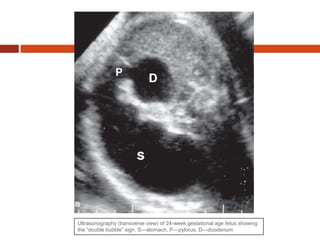

Duodenal obstruction is being

increasingly diagnosed prenatally. The

prenatal sonographic diagnosis of DO

relies on the demonstration of the “double

bubble” sign, which is due to the

simultaneous distension of the stomach

and the first portion of the duodenum. The

dilated stomach and duodenum appear

side by side across the midline of the

upper fetal abdomen

Ultrasonography (transverse view) of 24-week gestational age fetus showing

the “double bubble” sign. S—stomach, P—pylorus, D—duodenum